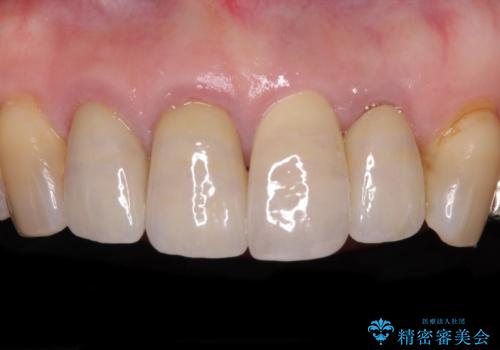

折れてしまった前歯 インプラントによる補綴治療